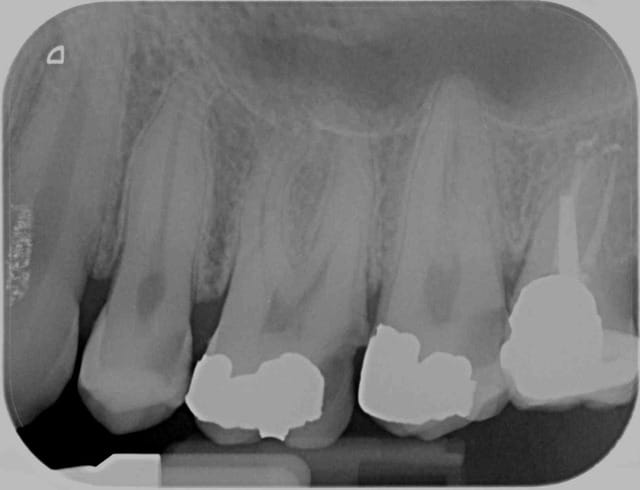

L'exemple de la 5 et de la 7 avec la dent absente au milieu, c'est vraiment typique du truc qui ne marche que dans la pub ou alors cinq minutes....

Là dans le cas montré ça a marché parce que c'est un RTE ! Même sans anesthésie ça aurait marché !

L'édentement comme ça c'est super facile, aiguille à transcorticale, on passe la corticale et on injecte, c'est le plus facile, sauf que jamais de la vie les deux dents ne seront endormies, ou alors pas suffisamment longtemps.

Je n'ai jamais trouvé que l'effet "soit par secteur" vanté dans la pub soit réel, en général plus on s'éloigne du point d'injection et moins l'effet dure longtemps.